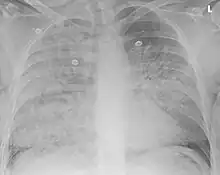

| Aspiration pneumonia in a ventilated person with a central line and nasogastric tube | |